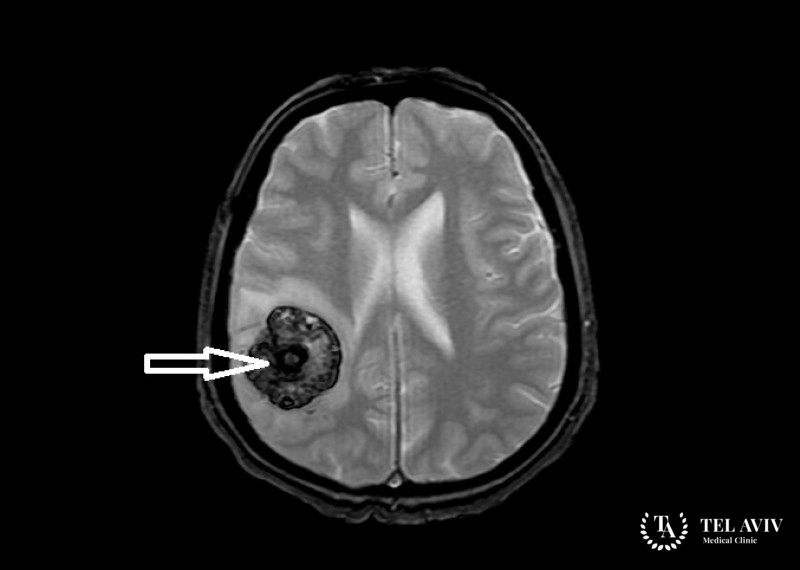

Из переродившихся клеток паутинной оболочки головного мозга образуется опухоль, имеющая округлую форму и расположенная в твердой оболочке мозга. В основном […]